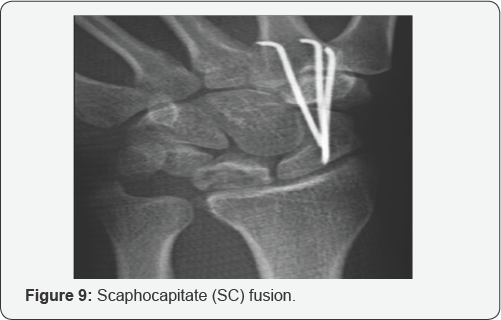

The use of STT fusion has waned in recent years because of complications and longer-term follow-up that has revealed decreased success rates [14] (Figure 9). Several authors have reported scapho capitate (SC) fusion. Biomechanically, this fusion has been shown to reduce strain at the radiolunate joint by about 10%. Some authors prefer this fusion because it requires only one fusion site and is technically easier to perform.